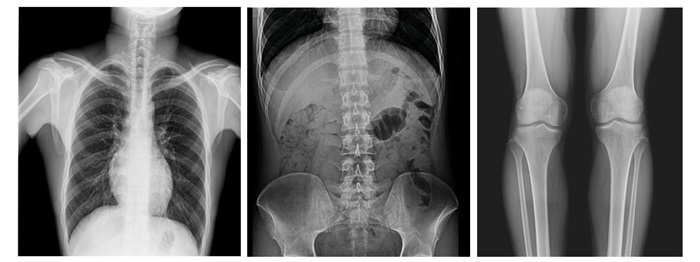

采用新一代動(dòng)態(tài)平板探測(cè)器,兼具動(dòng)靜態(tài)采集功能,輕松實(shí)現(xiàn)數(shù)字?jǐn)z影、數(shù)字胃腸、數(shù)字透視、數(shù)字造影、實(shí)時(shí)高清點(diǎn)片、視頻保存和回放等功能,滿足多科室臨床檢查需求。

高幀率動(dòng)態(tài)平板,高清成像

17×17英寸大幅面成像,一次曝光即可實(shí)現(xiàn)胸部、腹部全覆蓋,無(wú)需移動(dòng)即可觀察整個(gè)動(dòng)態(tài)過(guò)程,避免拖尾、噪聲對(duì)圖像的影響,避免漏診誤診;最高30/s采集幀率,動(dòng)態(tài)影像更流暢,便于使醫(yī)生觀察細(xì)微病變,提高診斷的準(zhǔn)確性。